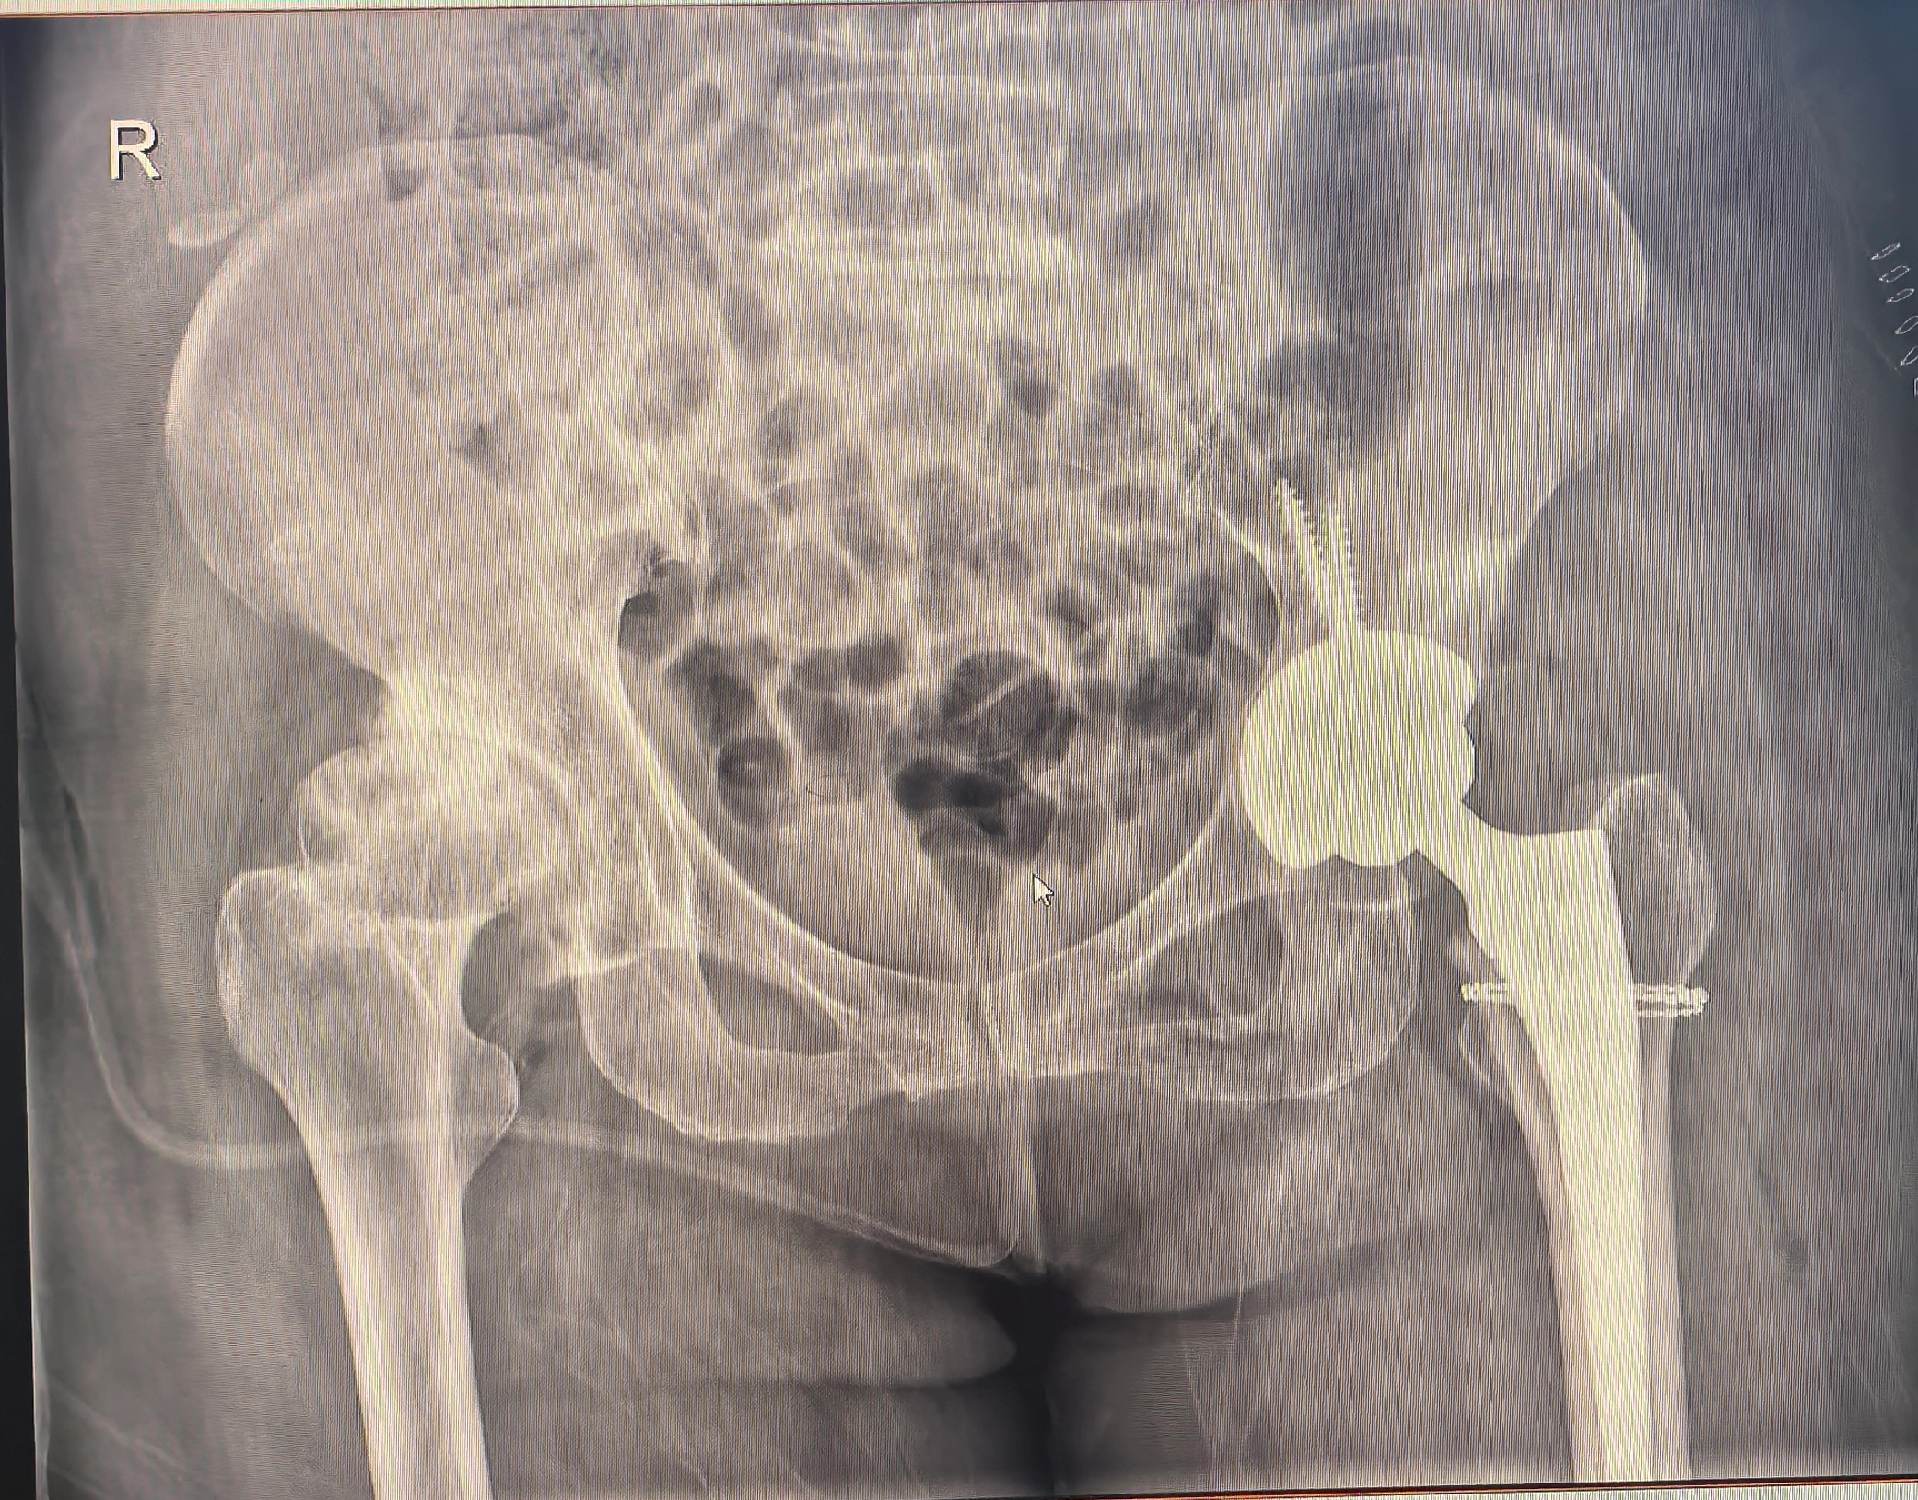

DDH,髋关节置换,髋关节发育不良。DDH髋关节置换,术前备的垫块,术中适当增加臼杯磋磨深度后包容性>80%,所以就没再放垫块,以最少的花费和最小的损伤让病人“髋”心🌹